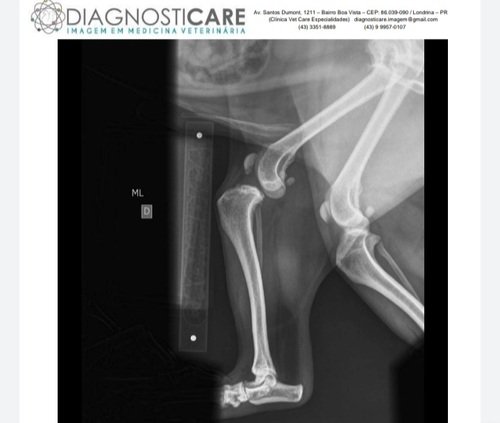

JERRY ROMPEU LIGAMENTO PRECISA DE CIRURGIA